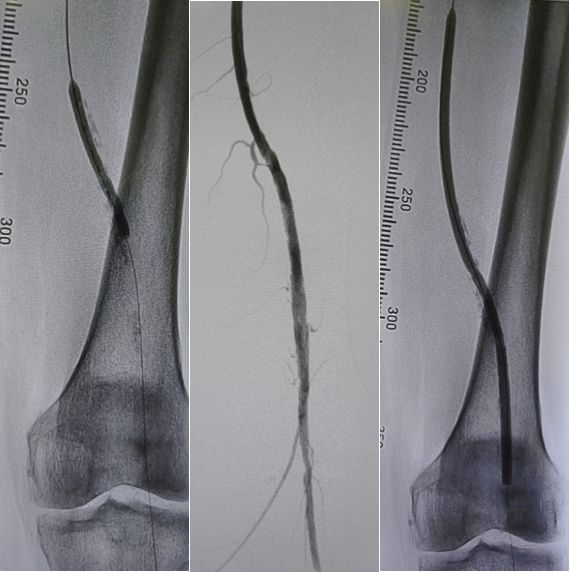

病例1(股腘动脉CTO):

一例重度间歇性跛行患者,导丝通过股腘动脉CTO病变后,若仅凭DSA判断,可能直接进行Rotarex减容。但IVUS检查发现导丝实际位于内膜下(假腔)。此时若进行减容,风险极高。术者遂调整策略,改用球囊扩张后植入Viabahn支架,成功避免了严重并发症。